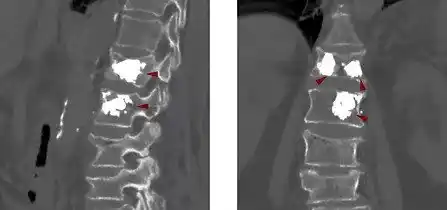

ezgif 5 dc6da9dc69Η κυφοπλαστική είναι μία διαδερμική μικροεπεμβατική μέθοδος αντιμετώπισης καταγμάτων της σπονδυλικής στήλης (συνήθως της θωρακικής και οσφυϊκής μοίρας) με την ενίσχυσή τους με ειδικό οστικό τσιμέντο.

Μέσα στον σπόνδυλο εισάγεται ένα ειδικό μπαλόνι το οποίο φουσκώνει και αποκαθιστά το σχήμα του σπασμένου σπονδύλου και το εύρος του σπονδυλικού σωλήνα, ενώ ταυτοχρόνως ανορθώνει τον σπόνδυλο επαναφέροντάς τον στο αρχικό του σχήμα και θέση.

Το κενό που δημιουργείται όταν ξεφουσκώσει το μπαλόνι, γεμίζει με οστικό τσιμέντο, με αποτέλεσμα να ενισχυθεί και να σταθεροποιηθεί το σπονδυλικό σώμα.